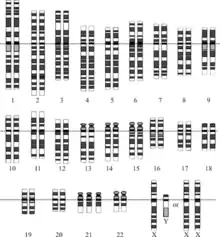

- Fetal karyotype can be used for the screening of genetic diseases. This can be obtained via amniocentesis or chorionic villus sampling (CVS[31])